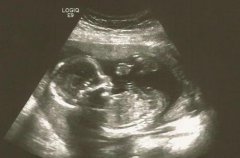

我是八月二十八,农历七夕的预产期。八月二十六八点整顺产男宝,医生说当天晚上二十几个孩子,只有两个女宝,这些小子们连个青梅竹马都得抢……孕期一直猜是男是女,没有问过B超医生,总结下我的症状,仅供娱乐……